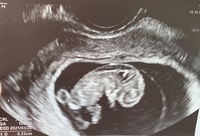

妊娠33週6日目の4Dエコー写真がこちら ↓↓ 胎児(赤ちゃん)の大きさ(推定体重):2112g(33w5d相当) 今回のエコー写真は本当にわかりにくいんですが。 。 。 また、足をピーンとのばしてかかとが頭の上の方に来てるみたいです。 このポーズ、前にも 妊娠9週目のエコー写真(胎児の大きさや状態) 7週目にクリニック(産婦人科)に行ってるから、次が9週目やな。 妊娠9週目のお腹のエコー写真が上↑のとおりや。 赤ちゃんの大きさが248mm、約2.48センチ!